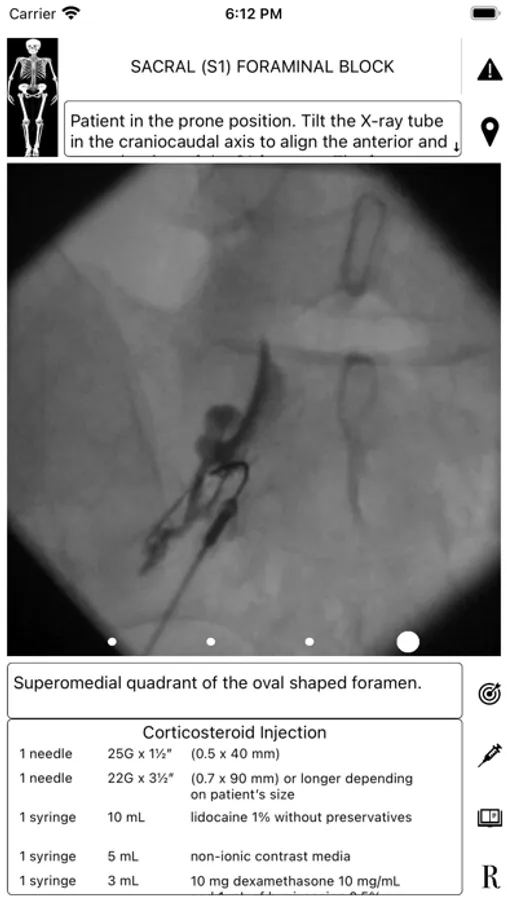

ArthroGuide targets residents, fellows, and physicians who perform fluoroscopically guided arthrograms and pain management injections, including spinal injections. It results from more than 25 years of experience in performing and teaching these procedures.

A visual interface facilitates a quick and efficient review of the information. Find information on patient positioning, puncture site, equipment used, products injected, and the steps to perform therapeutic injections and arthrograms preliminary to an MRI or CT scan. Access relevant references online using hyperlinks directly from within the application. Take advantage of procedural tips, recommendations, and cautionary statements.

ArthroGuide Screenshots